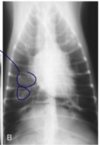

What are the thoracic imaging findings that suggest PHT (5 points)?

A

• Tortuous, blunted or dilated pulmonary arteries

• Asymettrical radiolucent lung fields

• Patchy or diffuse alveolar infiltrates

• Bulge in the pulmonary trunk

• Right sided cardiac enlargement